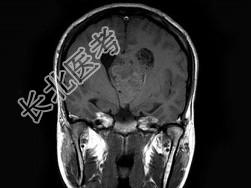

- 单项选择题男,32岁, 头痛呕吐半个月,MRI检查见脑室内占位, 最可能的诊断为 ( )

A、脉络膜丛乳头状瘤

B、室管膜瘤

C、髓母细胞瘤

D、脑膜瘤

E、未见异常